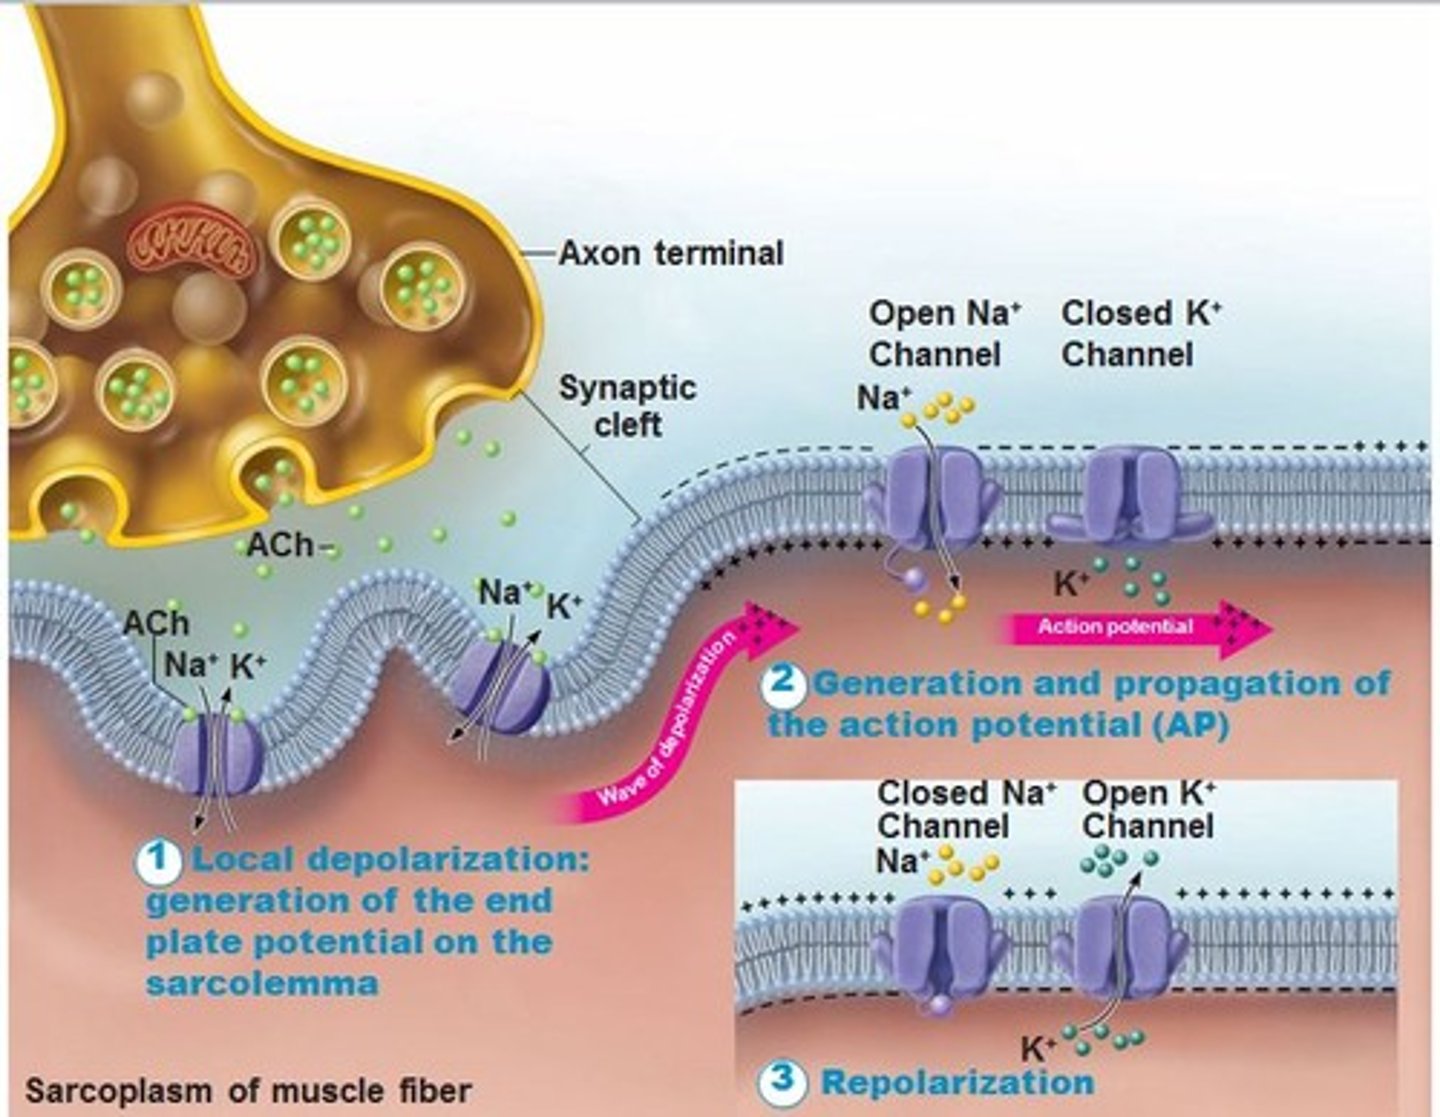

Action potential

a neural impulse (brief electrical charge) when a neuron sends information down an axon

Acetylcholine (ACh)

neurotransmitter released by motor neurons to activate muscles; plays a role in arousal, attention, memory, and motivation

Neural transmission

electrochemical communication within and between neurons and the final destination

Depolarization

a rapid rise in potential in a neuron triggered by the opening of sodium ion channels within the plasma membrane (a positive value)

Refractory period

after a neuron has fired; the time following an action potential during which a new action potential cannot be initiated